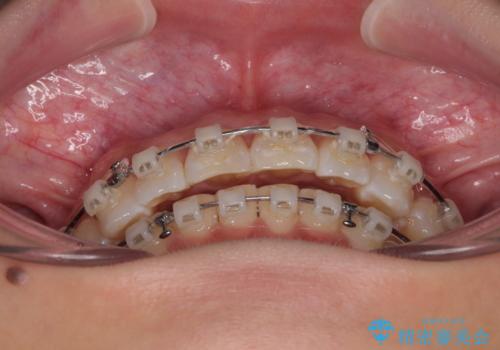

- 審美装置

- 上下前歯のデコボコとディープバイトを気にして来院された患者様です。

歯列全体に叢生があり、舌の突出癖が認められたため、突出癖が改善されない場合には口元が突出するリスクが考えられました。

マウスピースでもワイヤーでも対応可能でしたが、煩わしいことは避けたいとのことで、舌のトレーニングをしっかりと行っていただきながら、ワイヤー装置にて矯正治療を行うこととしました。